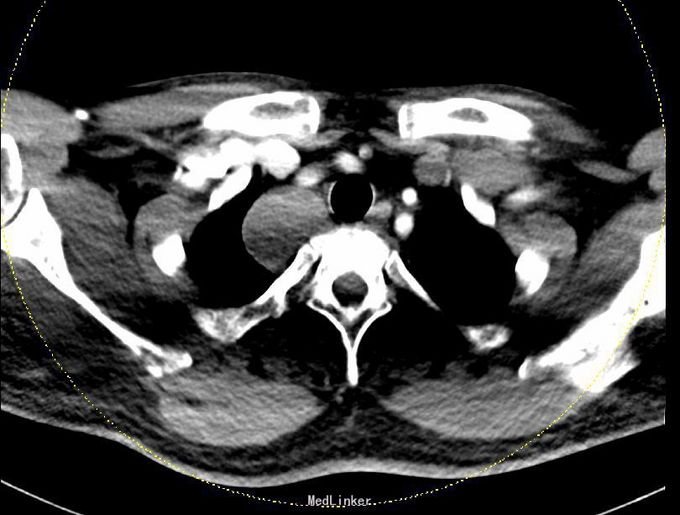

肺功能报告:MMEF轻度下降,V25中度下降,VE>10L。患者存在小气道气流轻度受限,过度通气,肺功能稍受损。 CT胸部增强扫描:右侧胸腔顶部见一大小约4.3*3.4cm软组织密度肿块,边界清楚,边缘光滑,与脊柱呈宽基底相连,增强后肿块明显均匀强化。第三肋骨可见致密结节影。意见:1、右后上纵隔占位,多系肿瘤:神经源性?淋巴源性或其他?2、心包及双侧胸膜稍增厚;3、右侧第3肋腋段致密结节,考虑骨岛可能。

诊断:1、 纵隔肿瘤(右后上,神经源性?淋巴源性?)2、脂肪肝3、脾大4、右第三肋骨骨岛形成5、右上颌窦囊肿 在全麻下右开胸右后上纵隔肿瘤切除术。术中见:1)胸内淡黄色积液50ml,无粘连;2)胸膜无种植;肿瘤对肺叶无侵犯, 肿瘤对心包无侵犯。3)肿瘤位于右后上纵隔约 4*3*3cm大小、包膜完整。4)淋巴结肿大及侵犯情况:无 5)术中冰冻结果:梭形细胞肿瘤,倾向神经源性 。6)术中特殊情况:无 完整切除肿瘤,术中出血不多,未输血,术后患者安返病房,给予对症、支持治疗。